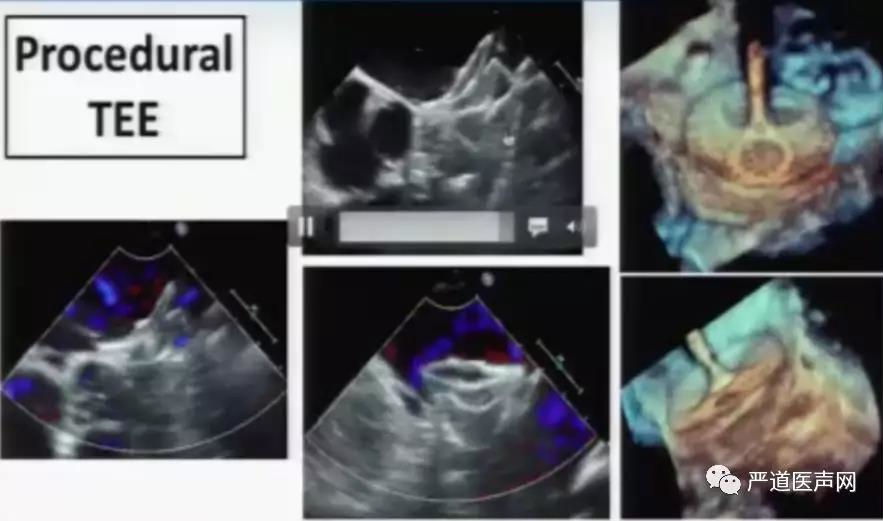

术中经食道超声影像

参考以往的手术经验,在反鸡翼型的左心耳封堵中,应用Amulet的“三明治”方案效果良好